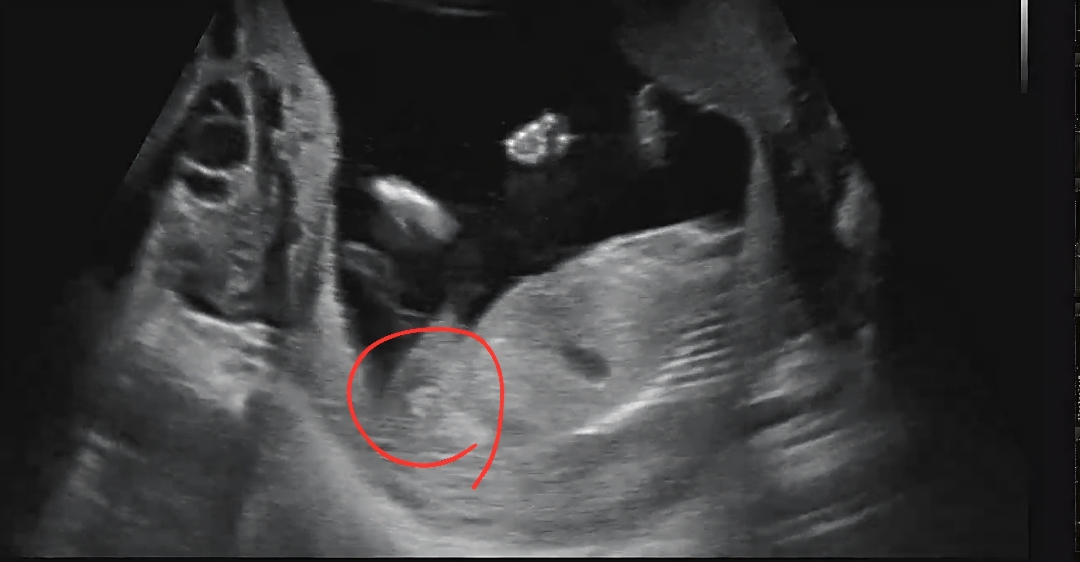

선배님들!! 16주 초음파 이거 삼지창일까요 미사일일까요?

16주차 옆모습인데 삼지창일지 미사일일지 아시는 분 계실까요?